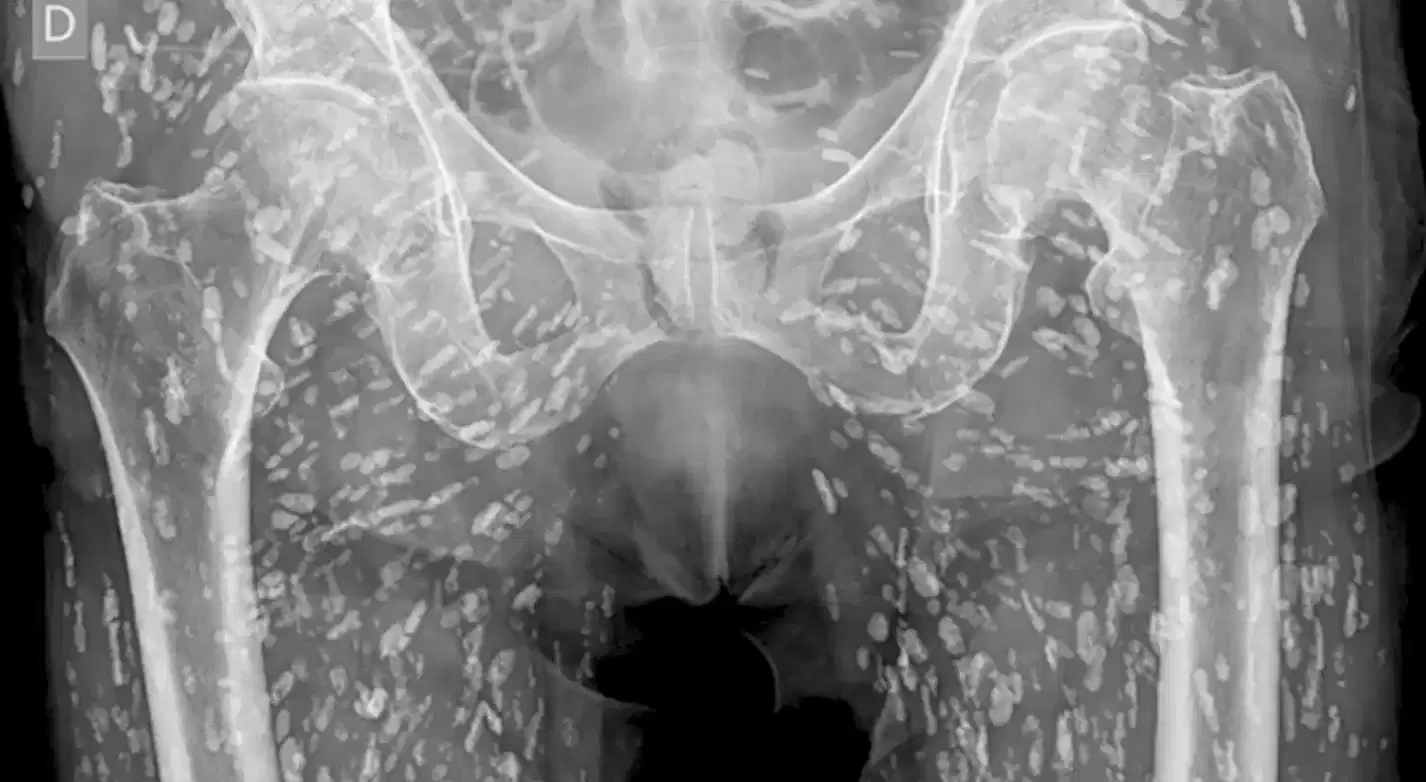

Sam Ghali, an Assistant Professor in Emergency Medicine at the University of Florida, shared the shocking images in a post on X, saying it was "one of the most insane X-Rays I've ever seen."

Speaking over the X-Ray pictures, Dr Ghali explained that the small white marks were dozens of calcified tapeworm eggs, which had been laid in the soft tissue of the man's pelvis.

The parasitic worms had made their way into the man's body after he at undercooked pork, a condition is known as cysticercosis.

This is where larval cyst of taenia solium make their way into the body. Once there, they can burrow into muscular and soft tissue and travel "throughout the entire body," Dr Ghali said.

He explained: "These cysts can travel anywhere throughout the entire body, heavily to the muscular and soft tissue of the hips and the legs. This condition comes from when the patient eats undercooked, or raw, pig. If just in the pelvis, they don’t pose a life-threatening problem. The problem is if they travel to the brain and lodge there.

"That can cause very serious issues. As you can imagine, that can lead to neurological symptoms like headaches, confusion, seizures and even death. The moral of the story is never eat raw pork."